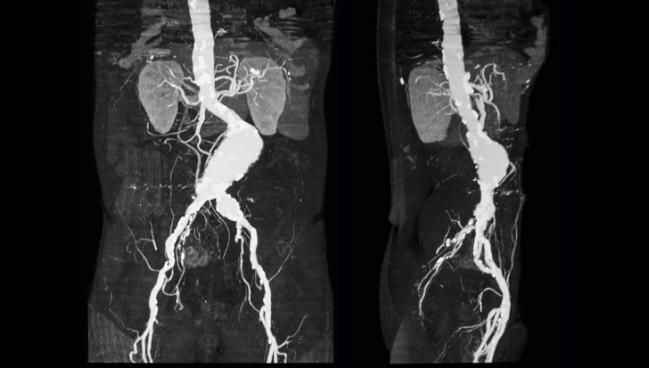

Abdominal aortic aneurysm (AAA) screening for men is standard in several countries, including the United Kingdom and Sweden. But new research suggests that women, who are less apt to develop AAAs, may not reap the same benefits from widespread screening programs, with the potential pitfalls of added cost and overdiagnosis.

AAA is four to five times more common in men than in women, and the benefits of screening women have rarely been studied. However, the effectiveness of male screenings has raised questions of whether these efforts should also extend to women.

In their study published in the August 11, 2018, issue of the Lancet, the researchers used data from reviews, clinical trials, and registries to create a simulated model testing the potential of AAA screening in women. What they found wasn’t encouraging.

The model followed the protocol of the UK National Abdominal Aortic Aneurysm Screening Programme (NAAASP), where all men at age 65 are screened for AAA via ultrasound. Sweeting et al estimated the number of positive screenings and clinical events for 10 million women and evaluated the cost-effectiveness of these AAA screenings over time.

Using the screening and treatment protocol currently used for men in the United Kingdom, the model detected 23% more AAAs than would be detected without screening in women ages 65 to 95 years. This translated to 7% fewer deaths due to AAA in the decade after screening and 3% fewer deaths due to AAA between the ages of 65 and 95.

The researchers found that 3,900 screenings would be necessary to prevent one AAA death in this population. Comparatively, fewer than 700 men need to be invited to screening to prevent an AAA-related death.